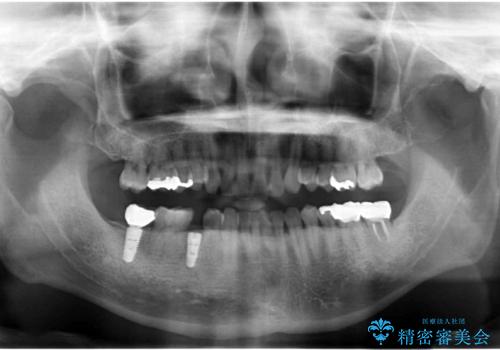

- 奥歯(右下5)のインプラントをご希望し来院された患者様です。

なるべく低予算でとのご希望により、アルファタイトインプラント(保証期間:3年)による治療を行いました。

インプラントの種類:アルファタイト

クラウンの種類:オールセラミッククラウン スタンダード